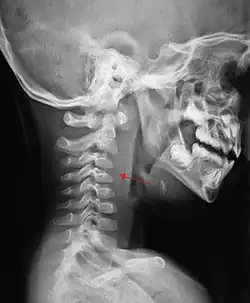

Ilustracja

Przedkręgowy obrzęk tkanek miękkich (oznaczony strzałką) u chorego z ropniem zagardłowym